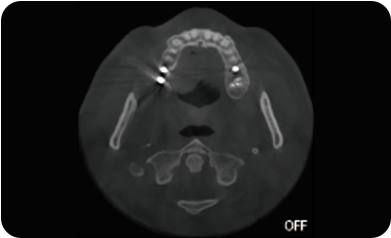

超能去伪 至臻影像

临床样片